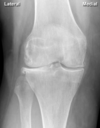

5

Osteoarthritis

Perfectly

Rheumatoid arthritis

Knee XR: gout vs pseudogout